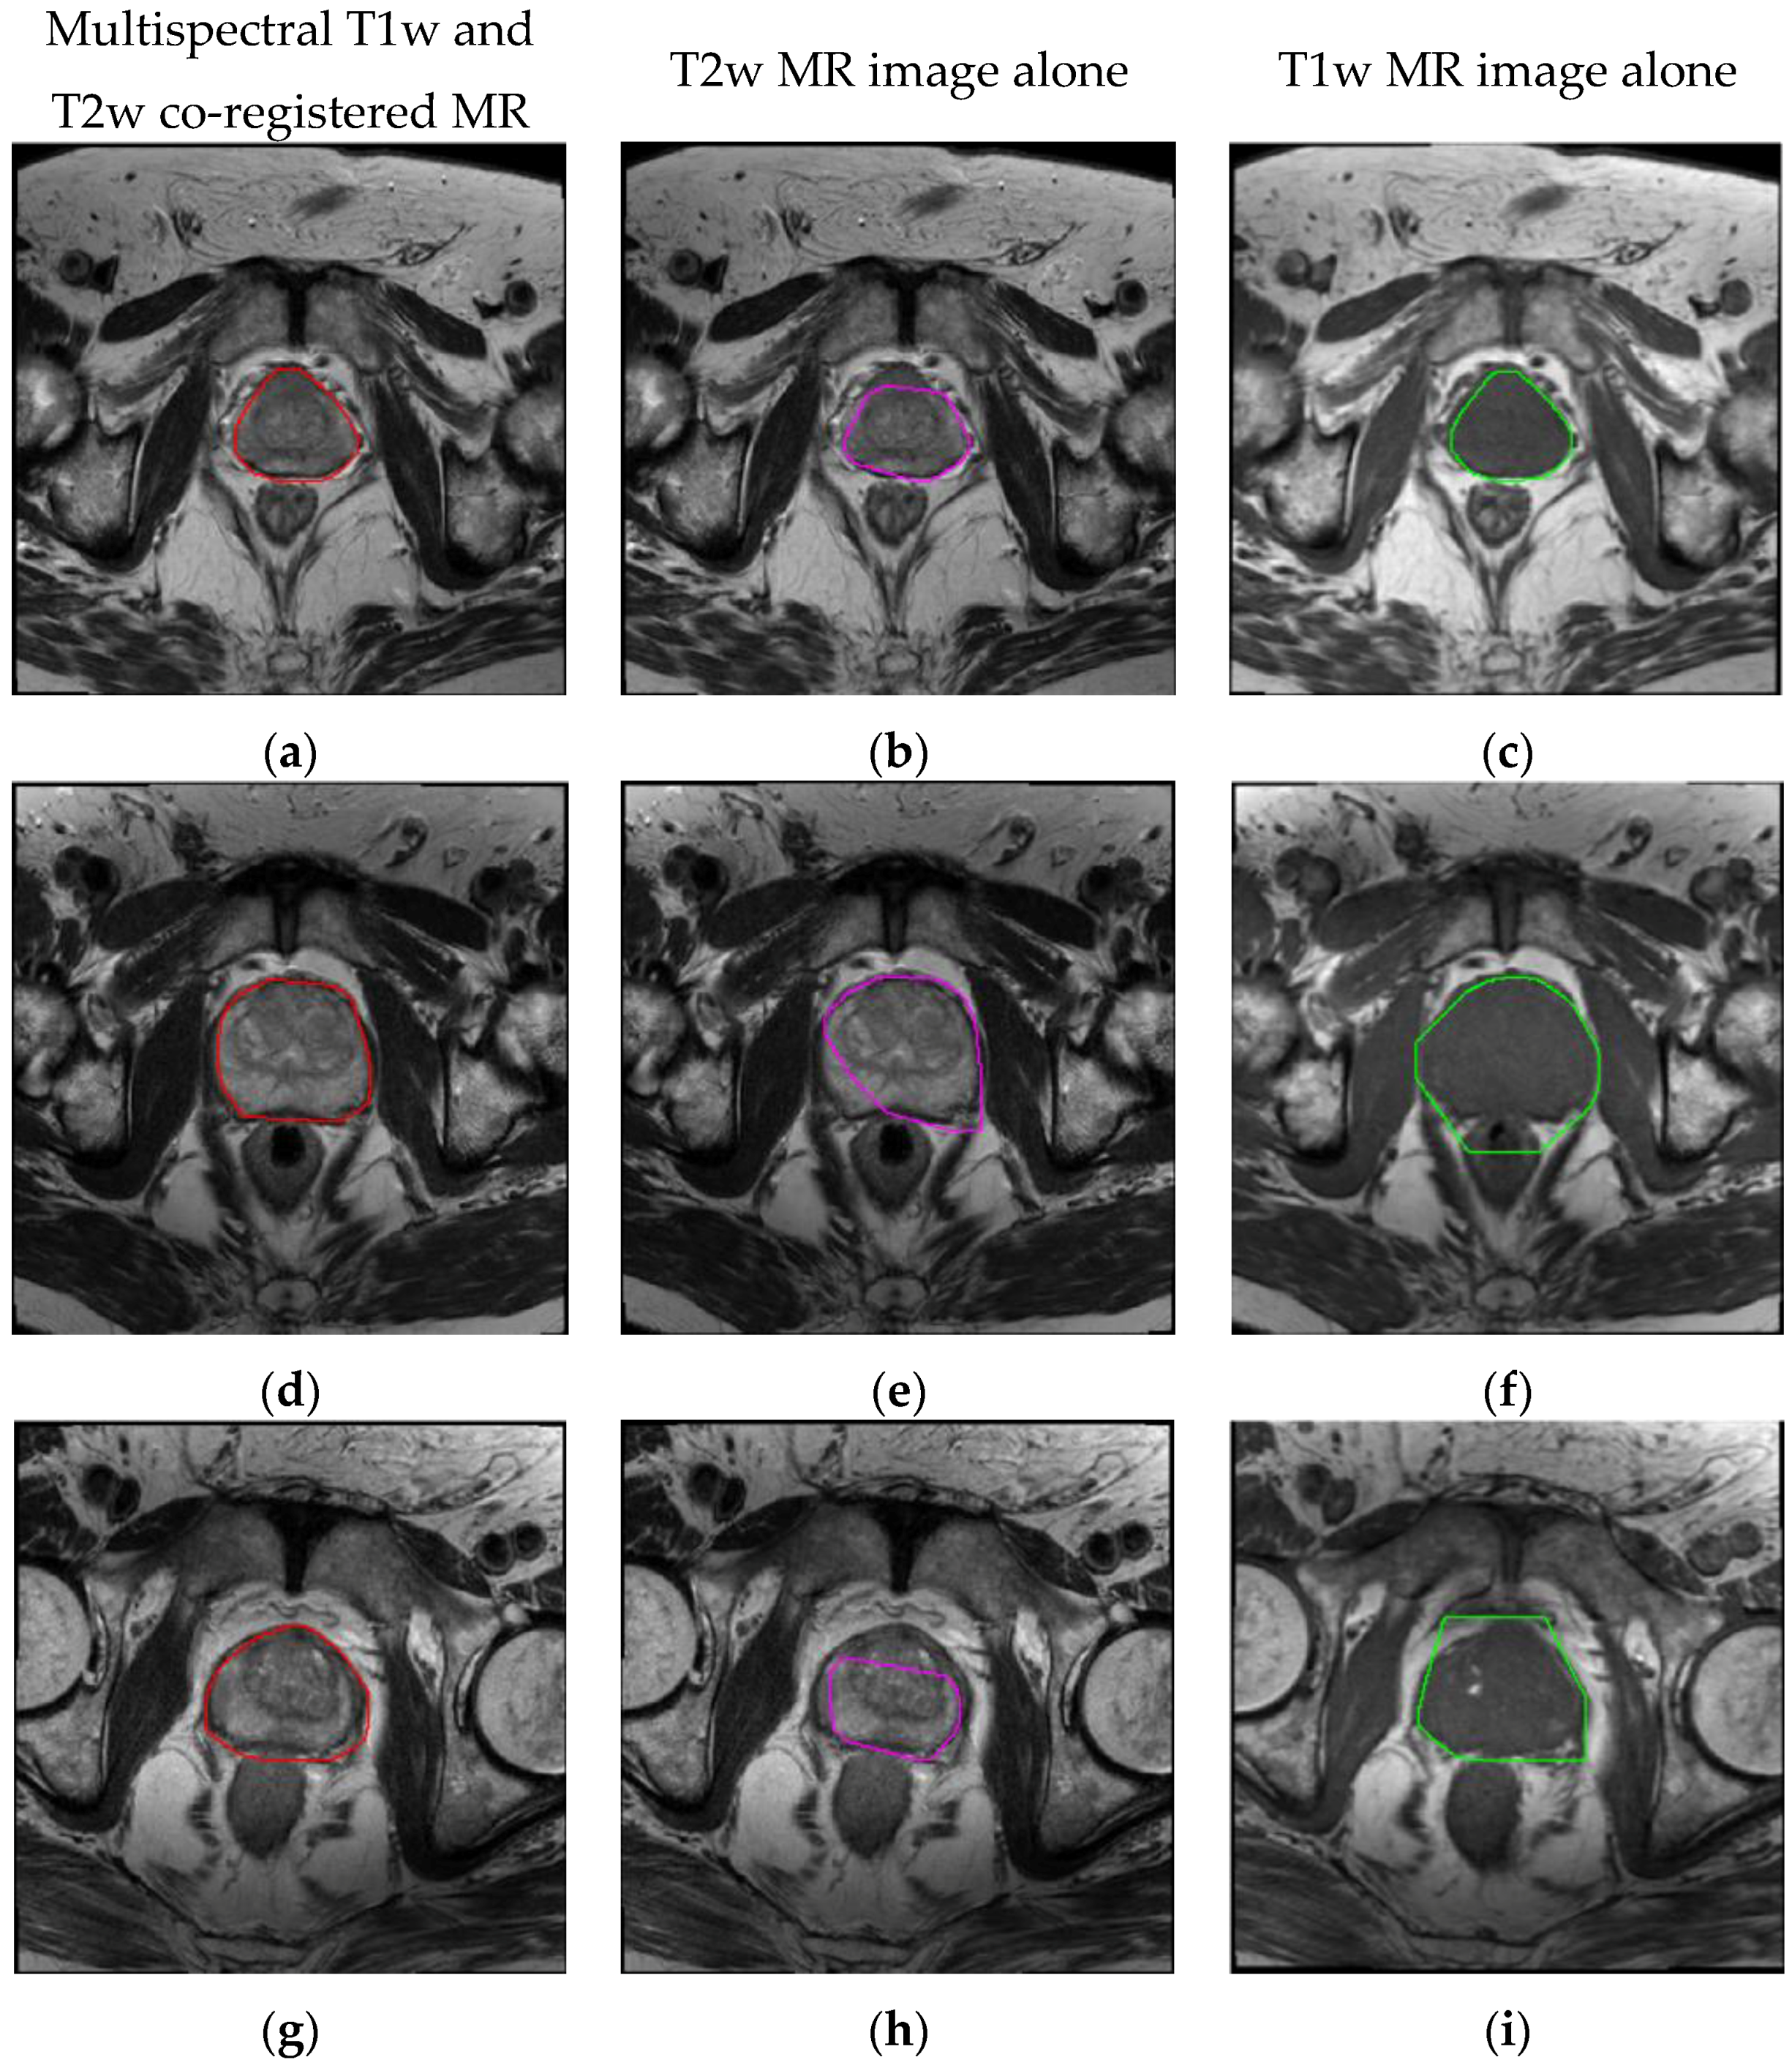

| MRI Data | DSC | JI | Sensitivity | Specificity | FPR | FNR |

| Multispectral | 90.77 ± 1.75 | 83.63 ± 2.65 | 89.56 ± 3.02 | 99.85 ± 0.11 | 0.15 ± 0.11 | 6.89 ± 3.02 |

| T2w alone | 81.90 ± 6.49 | 71.39 ± 7.56 | 82.21 ± 8.28 | 99.63 ± 0.25 | 0.37 ± 0.25 | 12.58 ± 8.49 |

| T1w alone | 82.55 ± 4.93 | 71.78 ± 6.15 | 93.27 ± 4.87 | 98.85 ± 0.58 | 1.15 ± 0.58 | 3.58 ± 4.95 |

| MRI Data | MAD (pixels) | MaxD (pixels) | HD (pixels) |

| Multispectral | 2.676 ± 0.616 | 8.485 ± 2.091 | 4.259 ± 0.548 |

| T2w alone | 4.941 ± 1.780 | 13.779 ± 3.430 | 4.535 ± 0.335 |

| T1w alone | 5.566 ± 1.618 | 14.358 ± 3.722 | 5.177 ± 0.857 |